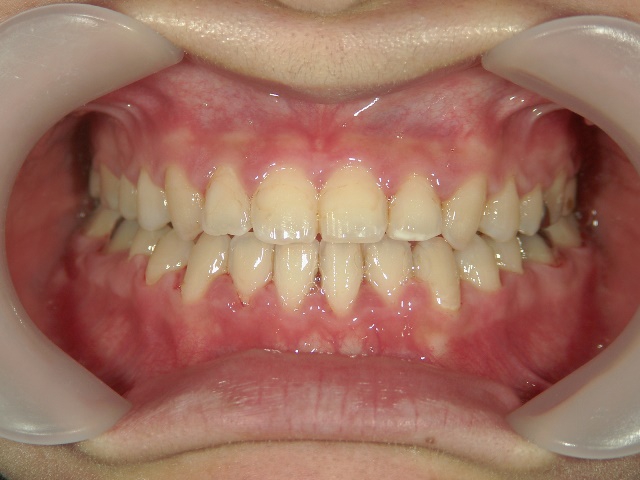

矯正歯科 治療前矯正歯科 治療前

主訴:受け口(反対咬合)を治したい

矯正歯科 治療前 急速拡大装置で上顎を広げた後、ワイヤーへ移行 非抜歯

no.31_7964_治療前_右 .JPGno.31_7964_治療前_正面 .JPGno.31_7964_治療前_左 .JPG